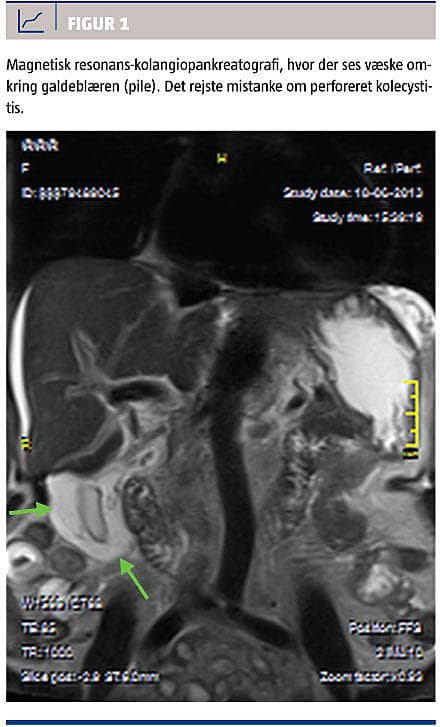

Ved den objektive undersøgelse fandtes hun ikterisk, men upåvirket. Abdomen var blødt og uømt. De vitale parametre var inden for normalområdet: blodtryk 143/80 mmHg, puls 82 slag pr. minut, iltsaturation 98%, respirationsfrekvens 14 pr. minut, temperatur 37,3 °C. Man fandt følgende værdier med referenceværdier angivet i parentes: forhøjede levergaldetal, alaninaminotransferase på 3.439 E/l (10-45 E/l), basisk fosfatase 307 E/l (35-105 E/l), bilirubin 201 mikromol/l (5-25 mikromol/l), leukocytter 6,5 × 109/l og C-reaktivt protein 6,4 mg/l. Der blev foretaget ultralydskanning af abdomen uden fund af galdesten. Der var let intrahepatisk galdegangsdilatation, og galdeblærevæggen fandtes fortykket, op til 13 mm. Under indlæggelsen fik hun smerter ved galdeblærestedet og yderligere stigning i bilirubinkoncentrationen til 285 mikromol/l (5-25 mikromol/l), hvorfor man valgte at udføre magnetisk resonans-kolangiopankreatografi (MRCP), der viste lokaliseret væske omkring galdeblæren, hvilket gav mistanke

om perforation (Figur 1). Der kunne ikke påvises intra- eller ekstrahepatisk galdegangsdilatation.